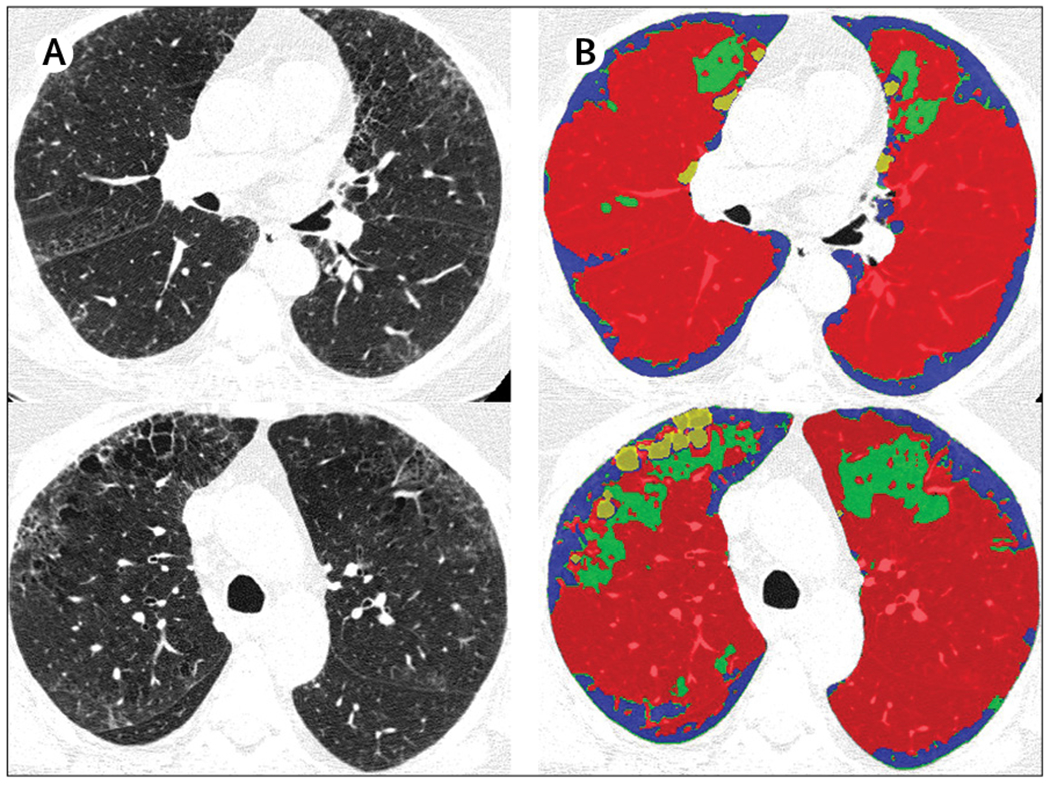

Description:The term interstitial lung abnormalities refers to specific CT findings that are potentially compatible with interstitial lung disease in patients without clinical suspicion of the disease. Interstitial lung abnormalities are increasingly recognised as a common feature on CT of the lung in older individuals, occurring in 4-9% of smokers and 2-7% of non-smokers. Identification of interstitial lung abnormalities will increase with implementation of lung cancer screening, along with increased use of CT for other diagnostic purposes. These abnormalities are associated with radiological progression, increased mortality, and the risk of complications from medical interventions, such as chemotherapy and surgery. Management requires distinguishing interstitial lung abnormalities that represent clinically significant interstitial lung disease from those that are subclinical. In particular, it is important to identify the subpleural fibrotic subtype, which is more likely to progress and to be associated with mortality. This multidisciplinary Position Paper by the Fleischner Society addresses important issues regarding interstitial lung abnormalities, including standardisation of the definition and terminology; predisposing risk factors; clinical outcomes; options for initial evaluation, monitoring, and management; the role of quantitative evaluation; and future research needs.